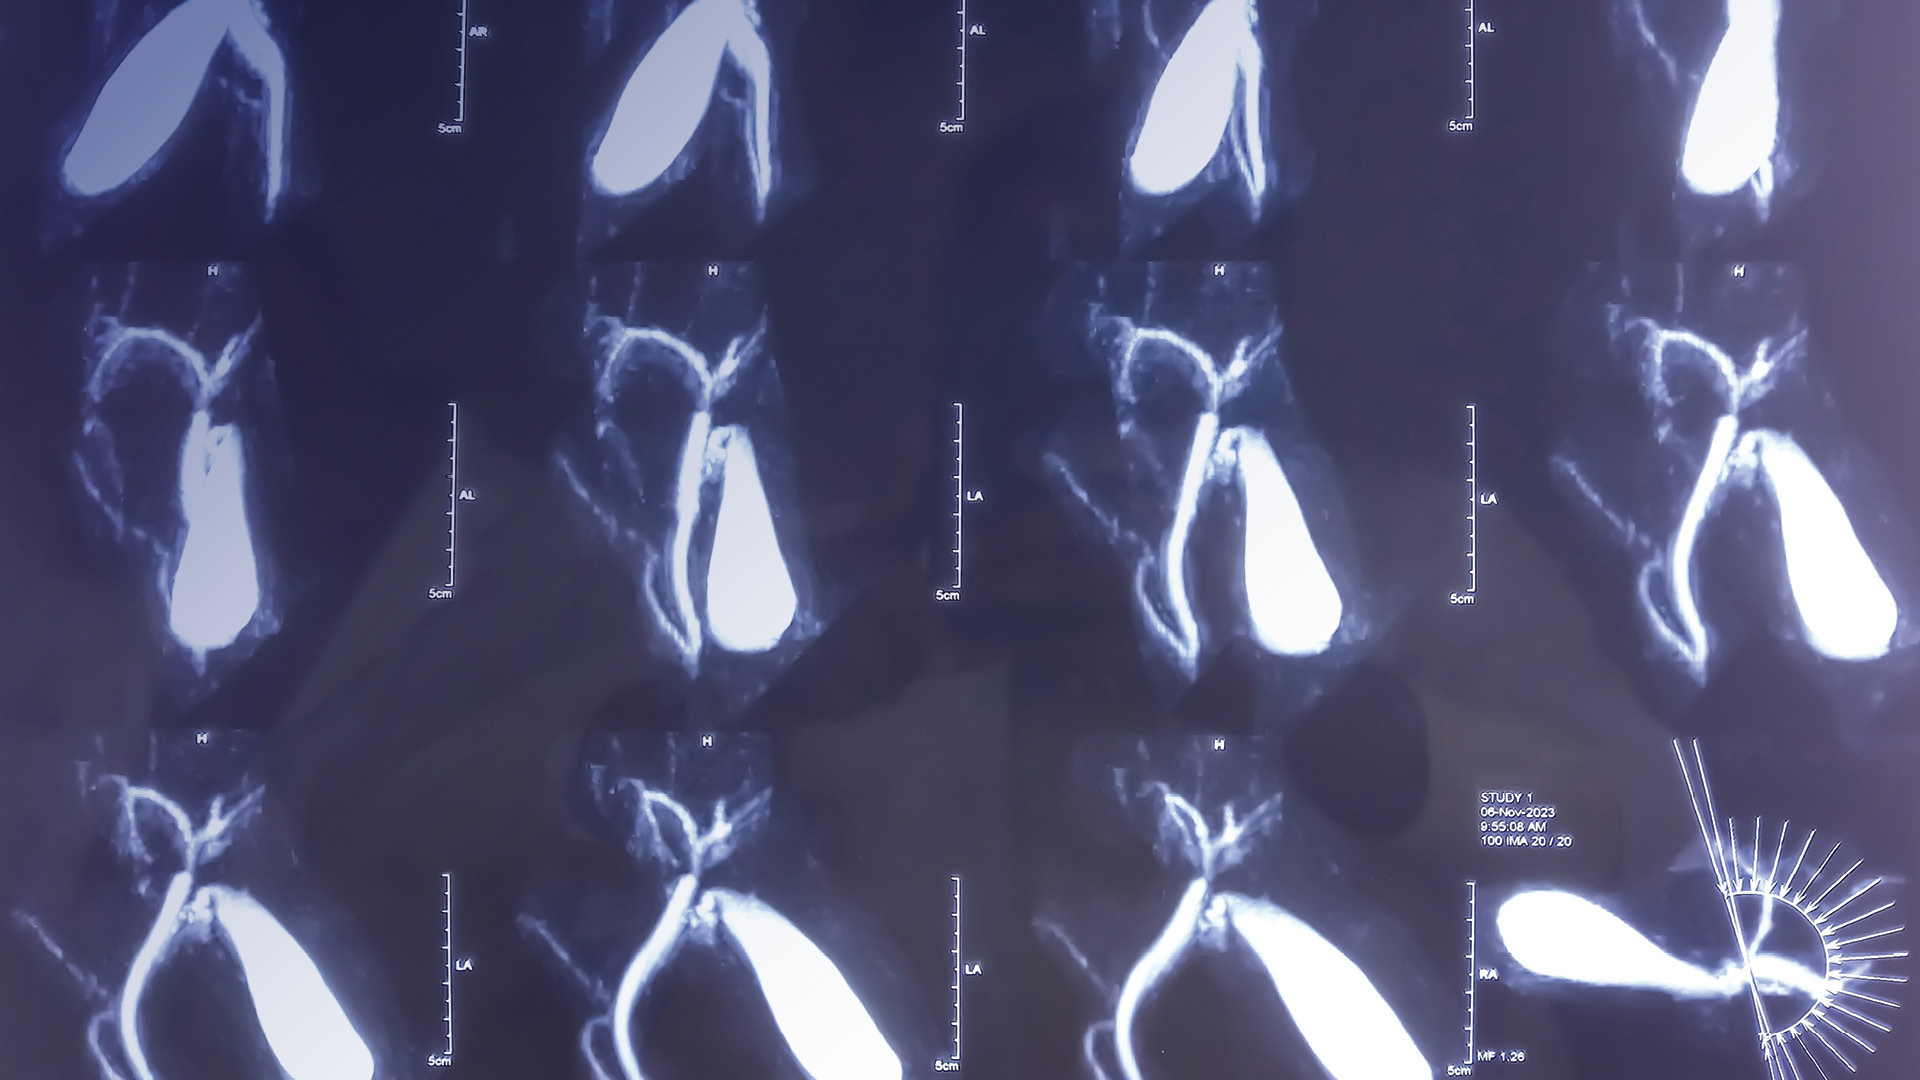

Despite the Dense Tissue and Early Breast Neoplasm Screening (DENSE) trial showing that the addition of magnetic resonance imagining (MRI) may lower the rate of interval cancers,4 the evidence was insufficient for the USPSTF to make recommendations for supplementary investigations due to lack of data regarding morbidity, mortality, or cancer detection.2 Nonetheless, some groups advocate for annual MRI screenings for high-risk women, although insurance approval remains a significant barrier.5

Both digital mammography and digital breast tomosynthesis (DBT) are endorsed by the USPSTF. However, DBT must be supplemented with synthetic or traditional digital mammography.2 Mammography has a sensitivity of 67.8% and a specificity of 75.0%, while DBT has a sensitivity of 90.8% and a specificity of 96.5% with the disadvantage of doubling the radiation exposure.10 DBT can reduce the masking effect seen in dense breasts and detect smaller tumors.11